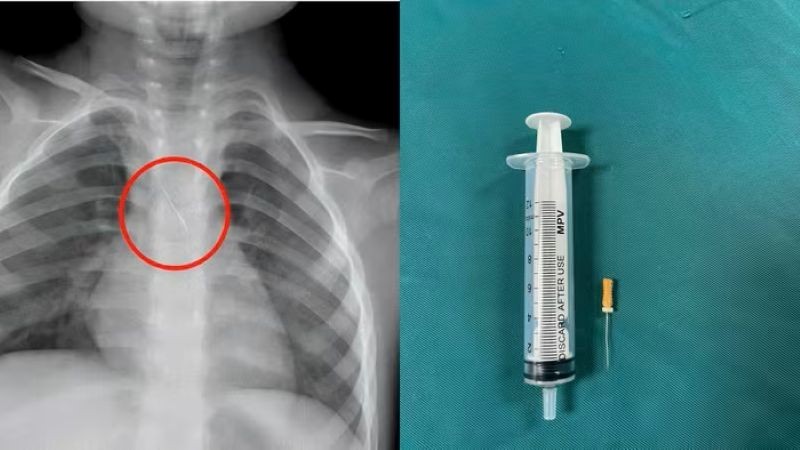

Quảng Trị: Kịp thời cứu cháu bé bị kim chọc tủy rơi vào đường thở

Sunday 2025-11-16 08:23Ngày 15/11, Bệnh viện Đa khoa tỉnh Quảng Trị cho biết vừa cấp cứu thành công một cháu bé 3 tuổi bị kim chọc tủy dài 22mm rơi vào đường thở. Dị vật trong đường thở của bệnh...